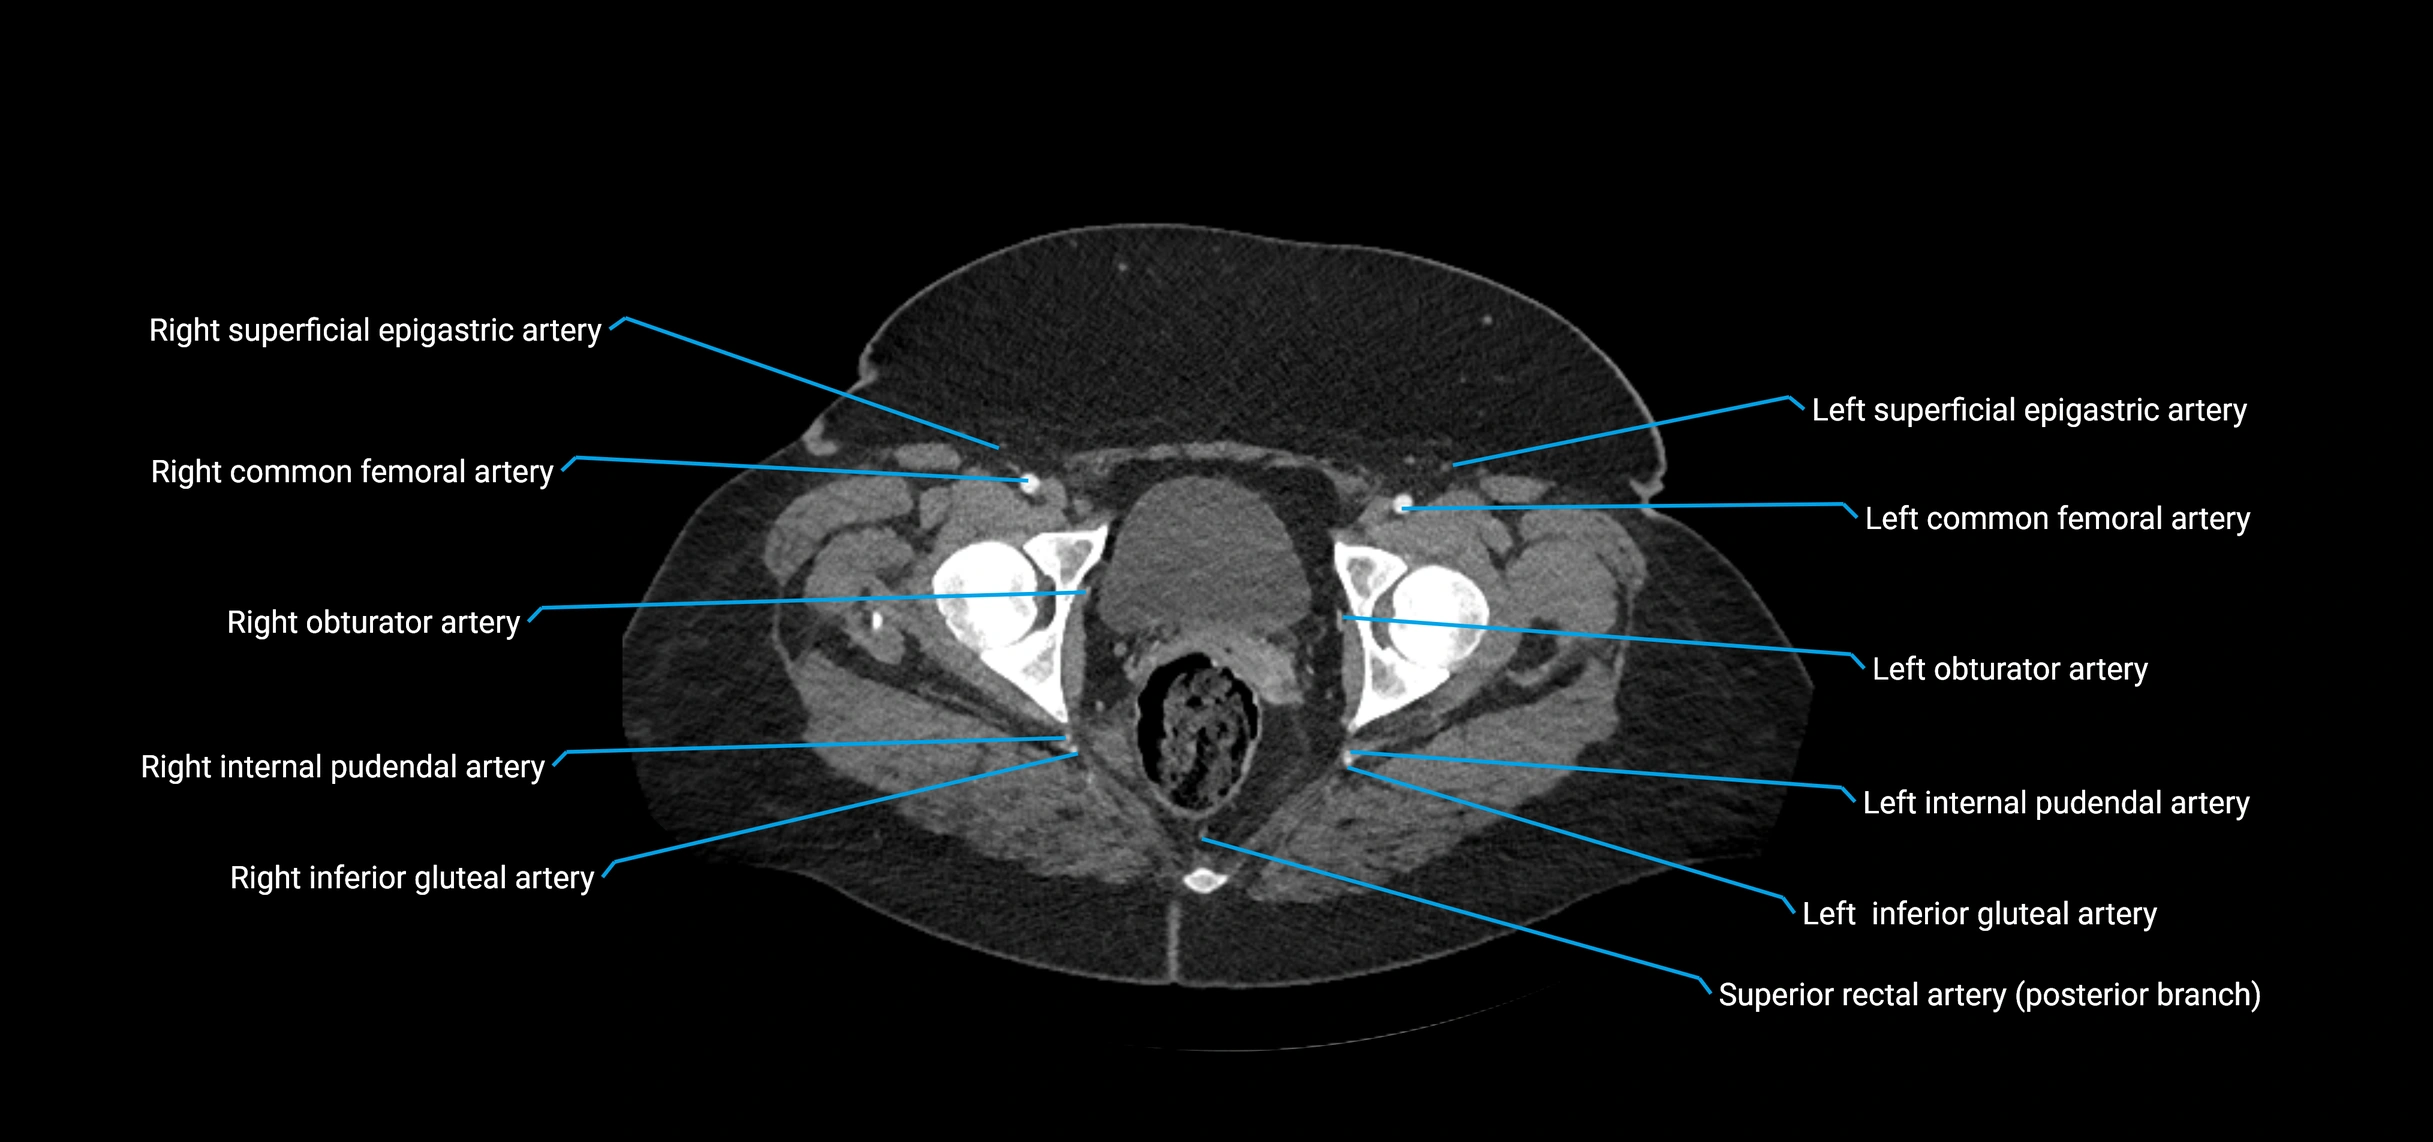

CT Appearance

Non-contrast CT:

• Appears as a tubular soft tissue structure anterior to vertebral bodies

• Calcified atherosclerotic plaques appear as hyperdense foci along the wall

• Useful for screening abdominal aortic aneurysm (AAA) size and mural calcification

Contrast-enhanced CT (CTA):

• Gold standard for abdominal aortic imaging

• Provides excellent detail of lumen, wall, aneurysm, thrombus, and branch vessels

• Multiplanar and 3D reconstructions help in aneurysm measurement, stent graft planning, and dissection evaluation

• Detects acute rupture, traumatic injury, or occlusion with high sensitivity

CT images

image